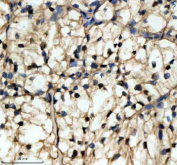

Immunohistochemical staining of NMNAT1 using anti-NMNAT1 antibody. NMNAT1 was detected in a paraffin-embedded section of human renal cancer tissue. Heat mediated antigen retrieval was performed in EDTA buffer (pH 8.0, epitope retrieval solution). The tissue section was blocked with 10% goat serum. The tissue section was then incubated with 2 ug/ml rabbit anti-NMNAT1 antibody overnight at 4oC. Peroxidase Conjugated Goat Anti-rabbit IgG was used as secondary antibody and incubated for 30 minutes at 37oC. The tissue section was developed using an HRP secondary and DAB substrate.